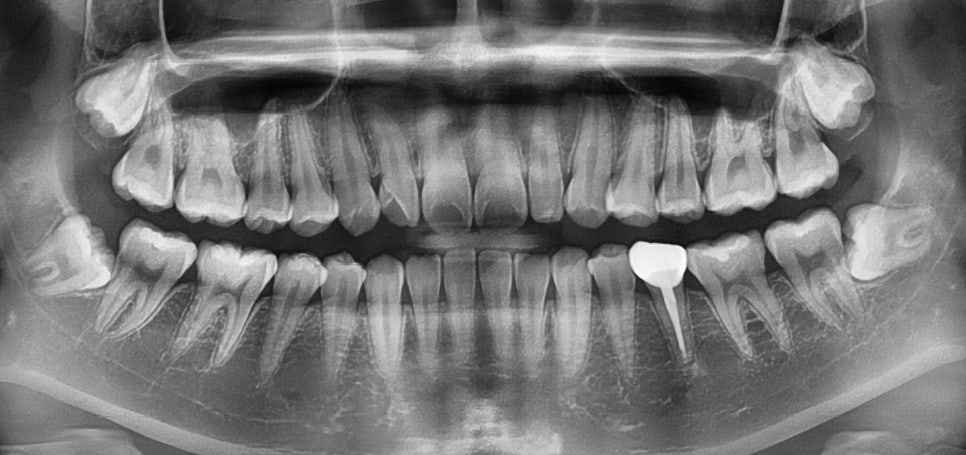

정밀한 검사를 위해

엑스레이를 비롯한 치근단 엑스레이,

턱관절 검사를 통해

치아 교정을 하여도

괜찮은지 확인하는 과정을 걸쳤습니다.

더불어, 왼쪽 위 측절치가

오른쪽 자연치에 비해

작은 것을 관찰할 수 있었는데요.